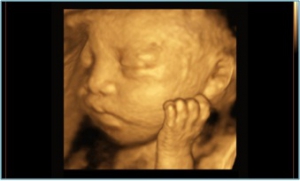

4D超音波検査

当院では、4D超音波診断装置を導入し、赤ちゃんの立体画像の撮影を行っております。

健診に来られないご主人やご家族の皆さんにも、動く赤ちゃんの画像を見てもらうことができます。ご出産前に一足早くお腹の赤ちゃんに会ってみませんか?